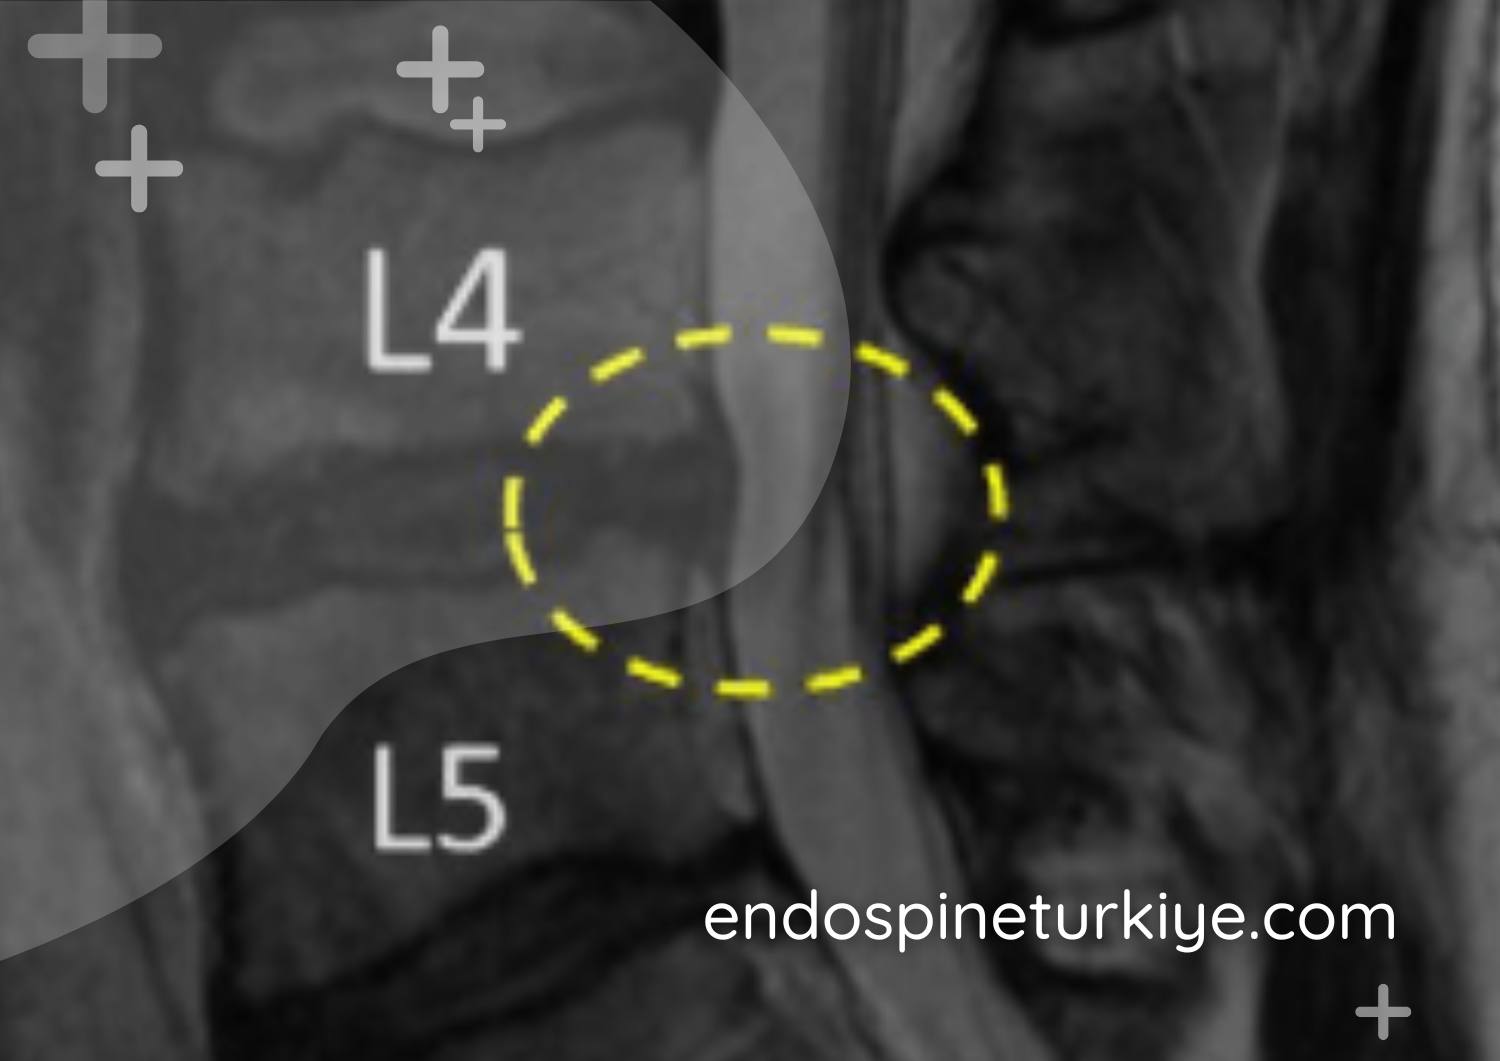

Tam kapalı dar kanal ameliyatı öncesi lomber MR - kanal darlığı teşhisi

Lomber MR görüntüsü - omurga kanalında daralma (spinal stenoz)